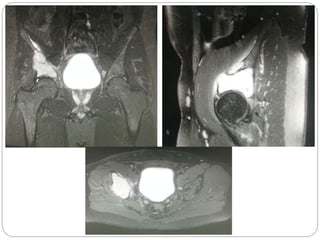

This document discusses 8 oncology cases. Case 1 involves a 40-year old female with right knee pain. Case 2 is a 28-year old male with a left subtrochantric fracture from a MVA who is now experiencing increasing left knee pain and swelling. Biopsy results showed high-grade osteosarcoma. Case 3 is a 30-year old female with breast cancer and bone metastases causing bilateral hip pain.